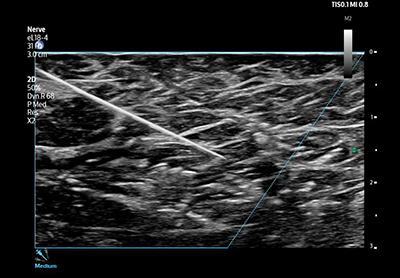

AutoScan によるリアルタイムでの明るさの自動画像調整や,撮像後の追加の最適化に寄与します。また,左室駆出率の自動算出や,穿刺針の視認性の向上を支援する機能に対応しています。